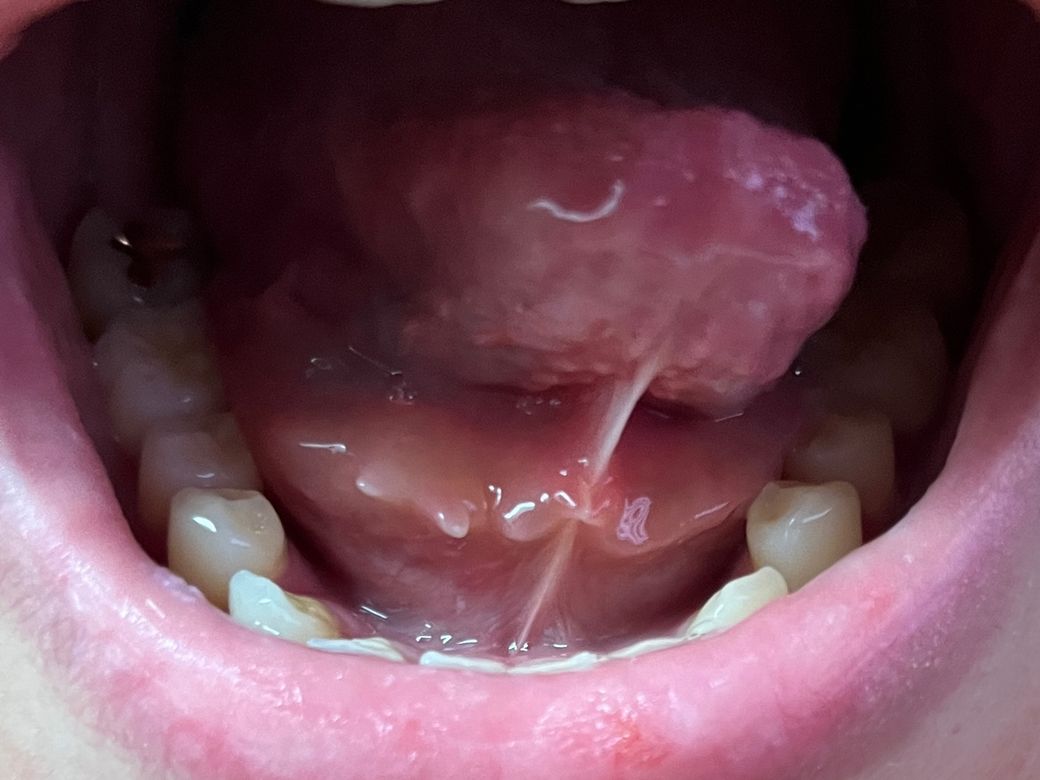

더불어 해당 증상이 수개월에 한 번꼴로 나타나다 보니 하룻밤 자고 일어나면 가라앉아있거나 호전되어 심각성을 느끼지 못했었는데 올해 초부터 아래 사진처럼 혀 아래에 침샘 주머니(?)가 돌출되고 침 넘김 시, 이물감이 느껴지며 불편합니다.

• 2번 째 사진